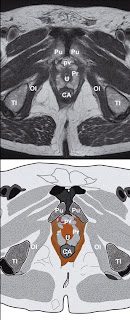

Neuf images « IRM » sont sélectionnées pour tenter

d’isoler les diff érentes structures constituant la

partie la plus profonde de la région périnéale. Elles

sont toutes en T2 (appareil GE 1,5 T). Les coupes

frontales sont eff ectuées avec une antenne endorectale,

alors que les coupes sagittales et axiales

sont réalisées à l’aide d’une antenne pelvienne.

Pour la lecture de chaque image, certaines coupes

ont été zoomées sur le périnée. En T2, les muscles

et les fascias apparaissent « gris foncé » (hyposignal).

– Coupes « axiales » (transversales ou horizontales)

en T2 avec antenne pelvienne : cinq coupes

sectionnent horizontalement le périnée. La

plus superfi cielle sous-pubienne passe par le

périnée antérieur superfi ciel (fi g. 8).

Plus profondément une seconde coupe se situe

dans la partie basse du périnée antérieur profond

(fi g. 9). La 3e plus haute située (fi g. 10) se

place à la partie inférieure des foramens obturés,

tangentiellement à la partie supérieure des branches

ischio-pubiennes et correspond à la coupe

« référante » du périnée antérieur profond. Audessus

En avant et latéralement, la région périnéale

profonde est limitée par les branches ischiopubiennes

(BI), naissant des tubérosités ischiatiques

(TI), bien observées en IRM sur les coupes

axiales (fi g. 10 et 11) et dirigées de l’arrière vers

l’avant en s’unissant au niveau de la symphyse

pubienne en hyposignal intense. La symphyse est

Elle est centrée par l’urètre dit « membraneux ».

Ses parois, en hypersignal (fi g. 5) limitent la lumière

urétrale centrale, collabée, en hyposignal.

Latéralement, l’urètre est entouré par le sphincter

en hyposignal modéré, avec un signal plus élevé

que les muscles striés de voisinage (muscles élévateurs

de l’anus et obturateurs internes). Sa moitié

supérieure est intraprostatique, dans la zone périphérique

en hypersignal. Le fascia pelvien viscéral

correspond au liseré d’hyposignal qui tapisse

la zone périphérique et qui recouvre les faces externes

du sphincter, de chaque côté, en débordant

latéralement pour atteindre le bord supéromédial

de chaque muscle élévateur de l’anus

(fascia pelvien pariétal). La moitié inférieure du

sphincter, extraprostatique, forme une cupule à

l’urètre qui change de direction. De chaque côté,

ce sphincter semble se prolonger latéralement

par une structure musculaire en hyposignal modéré

qui rejoint la branche ischio-pubienne homolatérale.

Il peut s’agir des muscles transverses

profonds droit et gauche qui comblent ainsi en

partie l’espace profond du périnée. Le fond de la

cupule s’intègre, sans limite nette décelable, dans